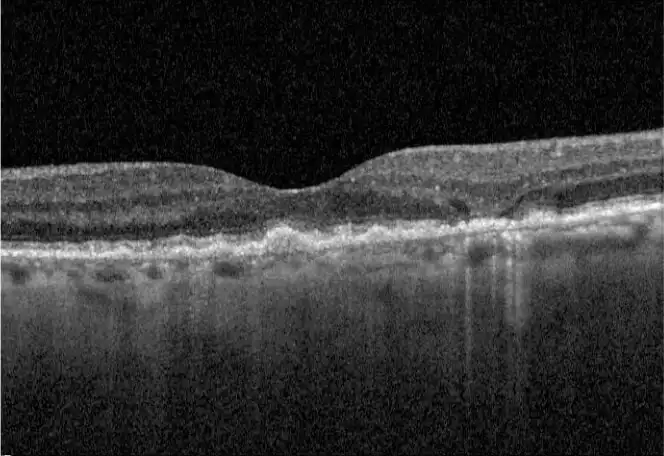

Neovascular AMD

- In clinical trials, use of IZERVAY was associated with increased rates of neovascular (wet) AMD or choroidal neovascularization (7% when administered monthly and 4% in the sham group) by Month 12. Over 24 months, the rate of neovascular (wet) AMD or choroidal neovascularization in the GATHER2 trial was 12% in the IZERVAY group and 9% in the sham group. Patients receiving IZERVAY should be monitored for signs of neovascular AMD.